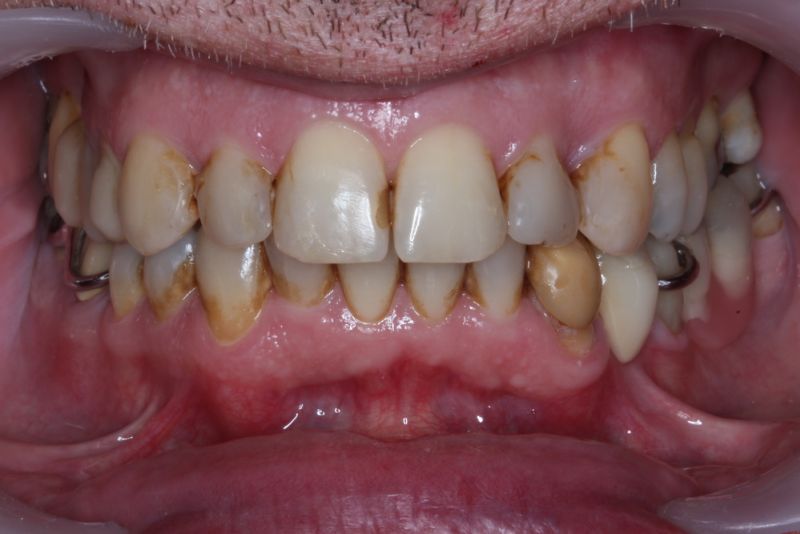

Erkennbar ist die massive Abweichung der habituellen Bisslage von der neuromuskulär zentrierten Bisslage.

Der Patient hat in den Jahren 2012-2014 eine kieferorthopädische Erwachsenenbehandlung durchführen lassen.